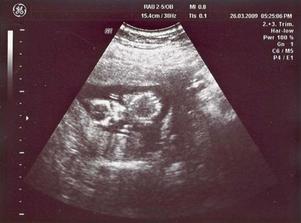

26/3 09 PORADNA 14 + 4 tt - přítel nesmí chybět, žížalka povyrostla, je to mrška neposedná, ani chvíli není v klidu, dr. má problémy vystihnout okamžik aby byla fotka z utz pěkná, nakonec máme fotečky dvě, na jedné jdou vidět oči - vypadá jak marťan 🙂), dr. slíbila že na příští KO už budeme vědět pohlaví ... čekání do 28/4 bude nekonečný